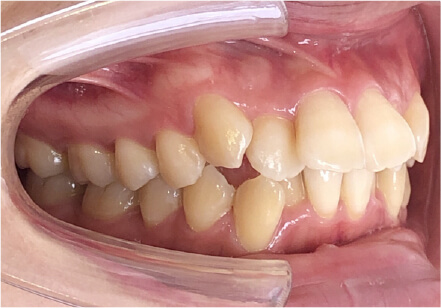

叢生の症例

11歳

/

女性

相談内容

上の前歯の歯並びが気になる(マイオスマイルからの移行)

カウンセリング・診断結果

インビザライン、拡大入れながらスペースを作成、下Eは出てきたら削りながら進める

治療内容・方法

全額アライナー矯正 クリアコレクト

術後の経過・現在の様子

クリアライナー使用

治療のリスク

痛み・歯根吸収・歯肉退縮・虫歯・後戻り

費用・治療期間

移行料金220,000円、月々16,500円、1年1ヶ月+myo2年3ヶ月